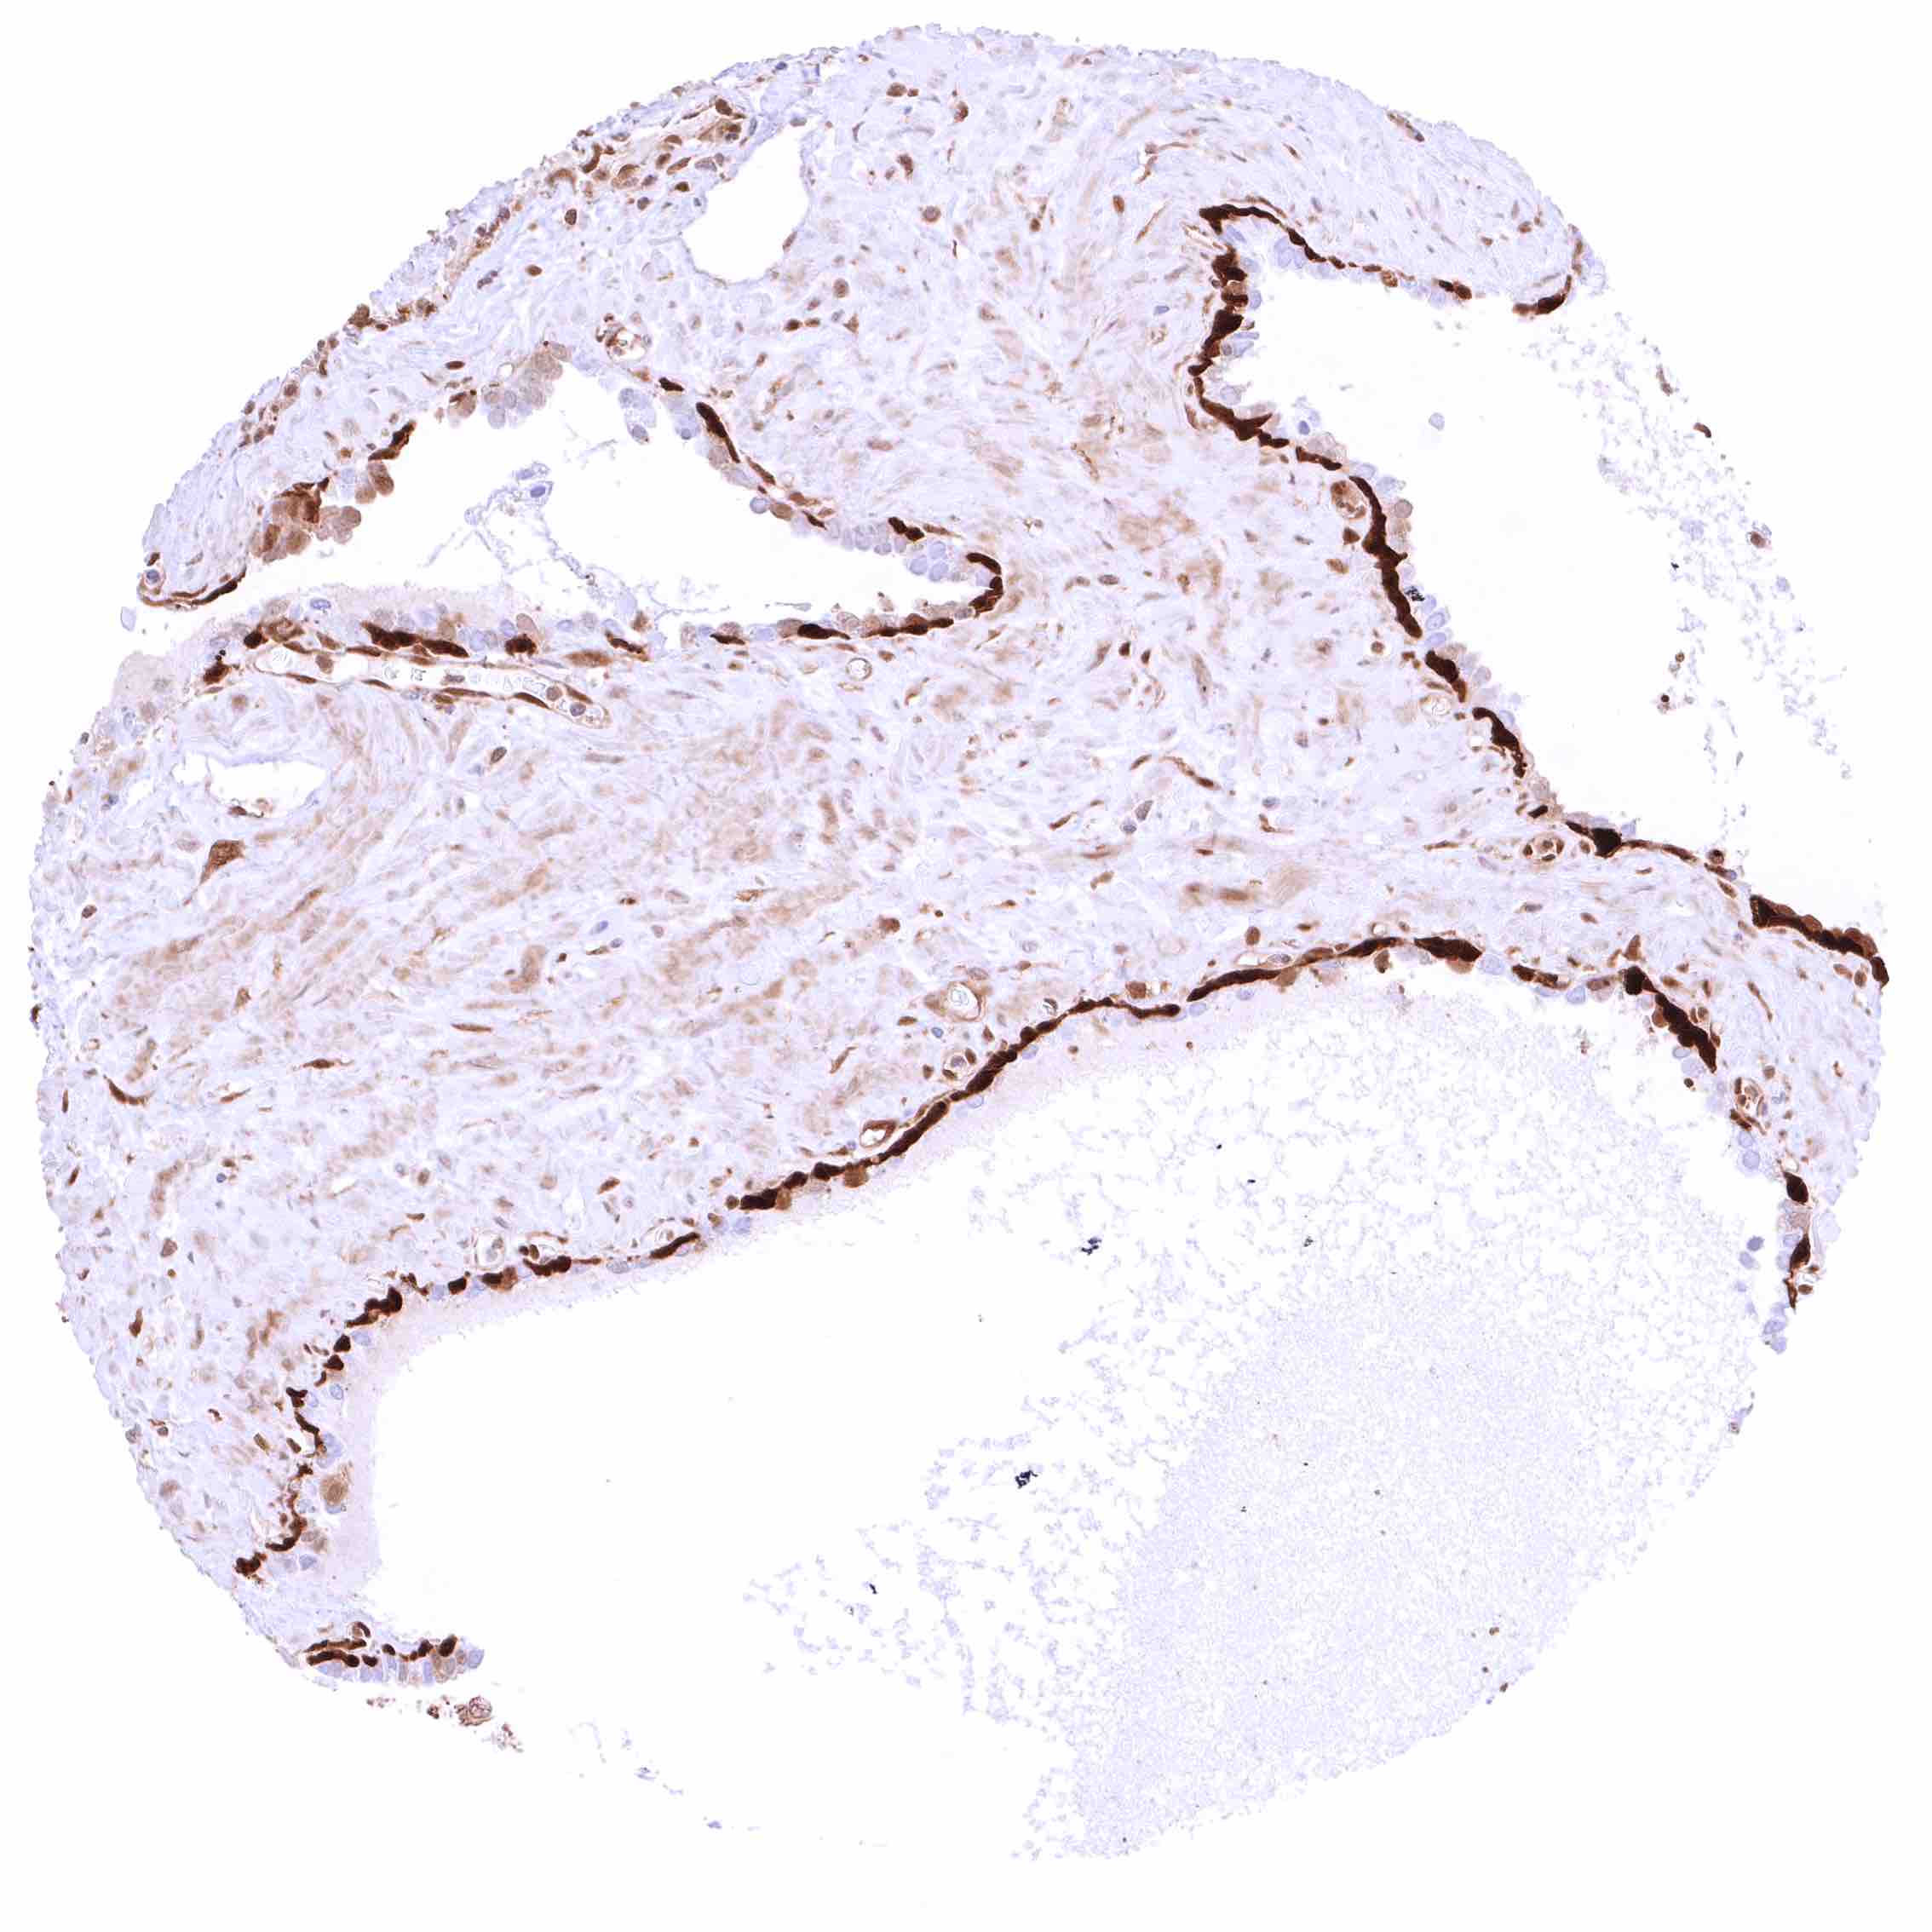

Urinary bladder, urothelium – Moderate to strong, predominantly cytoplasmic GSTP1 positivity of urothelial cells.

Urinary bladder, urothelium – Moderate to strong, predominantly nuclear GSTP1 positivity of urothelial cells.

Urinary bladder, muscular wall – Weak cytoplasmic GSTP1 positivity of smooth muscle cells.